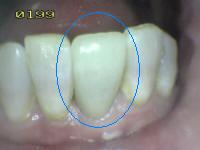

1 |

Sellador parcial |